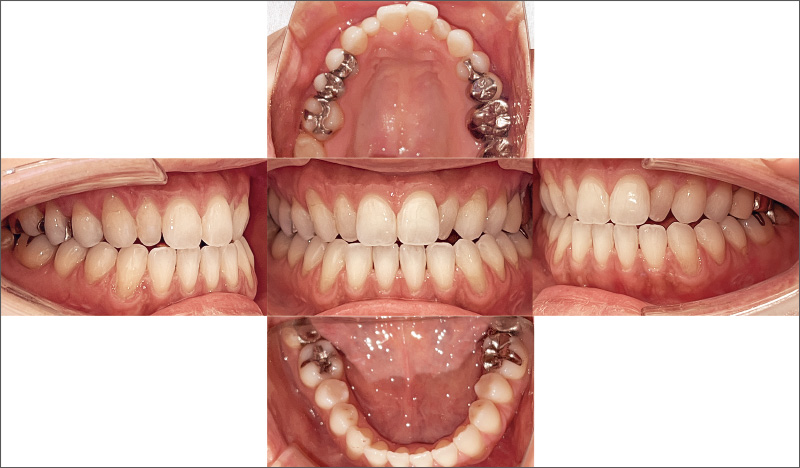

![[写真] 矯正治療後、₂にジルコニアフルクラウンを装着](/academic/dentalmagazine/wp-content/uploads/sites/2/2025/09/194-5_photo09.jpg)

症例2-3 矯正治療後、₂にジルコニアフルクラウンを装着。患者さんの主訴である審美回復を得ることができた。 -

![[写真] 術前と術後の比較](/academic/dentalmagazine/wp-content/uploads/sites/2/2025/09/194-5_photo10.jpg)

症例2-4 咬合における懸念点があり、今後も継続的なメインテナンスが必要と考える。本治療後に「インビザラインGo Plus」がリリースされ、第一大臼歯までの矯正治療が可能となったことは喜ばしいことと考える。